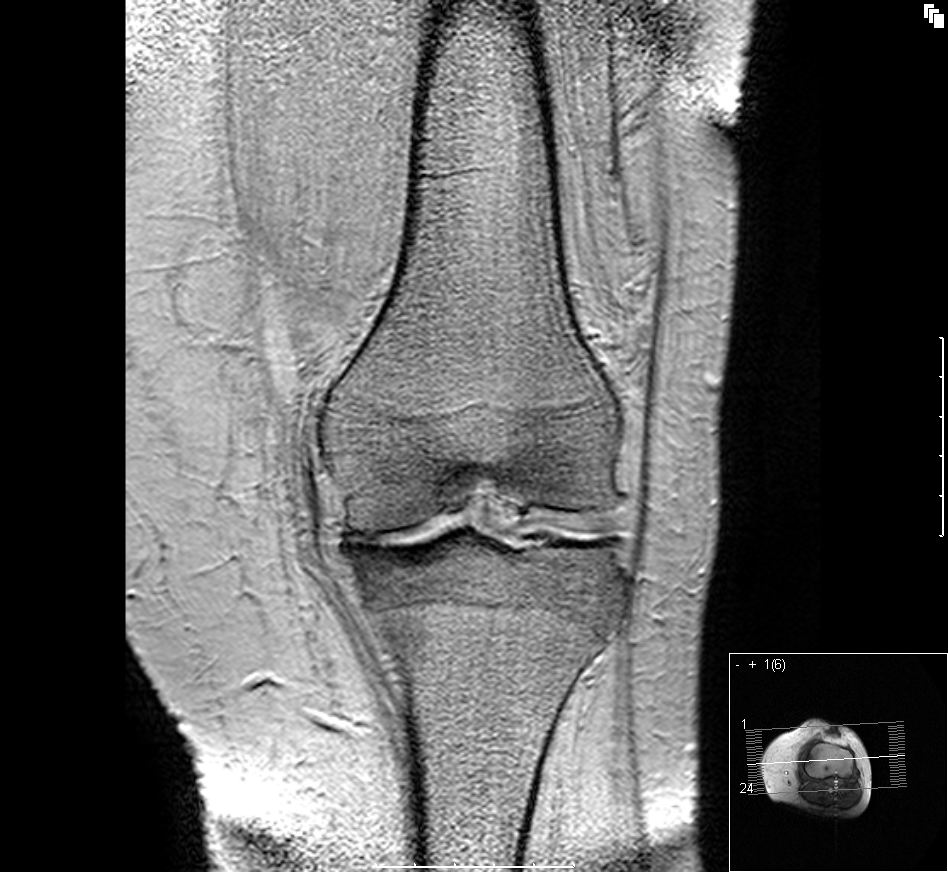

5. 진단

뼈관절염의 진단은 병력 청취 및 신체 검사를 통해 이루어지며, X-ray 촬영으로 확진할 수 있다.[52][53][54] X-ray 소견으로는 관절 간격 협소, 연골하 경화증(관절 주위 뼈 형성 증가), 연골하 낭종 형성, 골극 형성이 나타난다.[54] 다만, 단순 촬영 소견은 신체 검사 소견이나 통증 정도와 일치하지 않을 수 있다.[55]